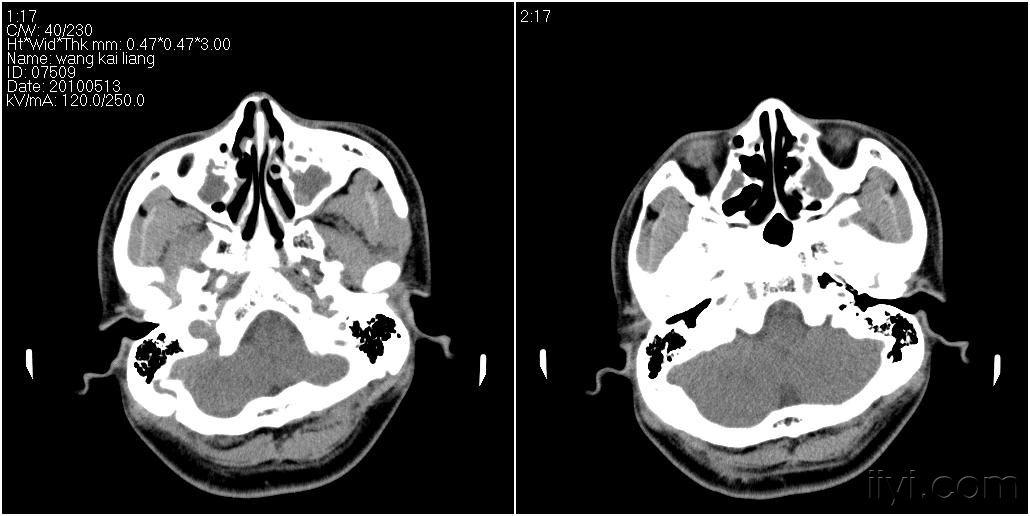

男性27岁患者要求头颅扫描发现蝶窦病变